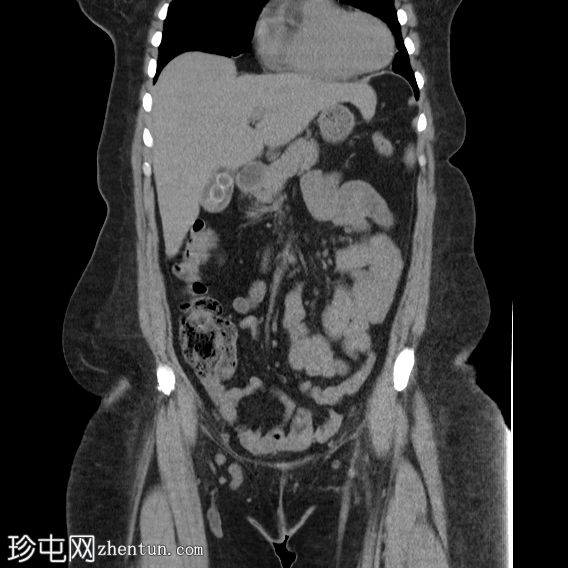

轴位

平扫

胆囊内可见多发大小不一的多面环状钙化胆结石。胆总管直径处于正常上限。胆总管内未见其他结石。

右侧肾中盏可见一非梗阻性结石(10.5 mm),CT值较高(900–1000 HU)。